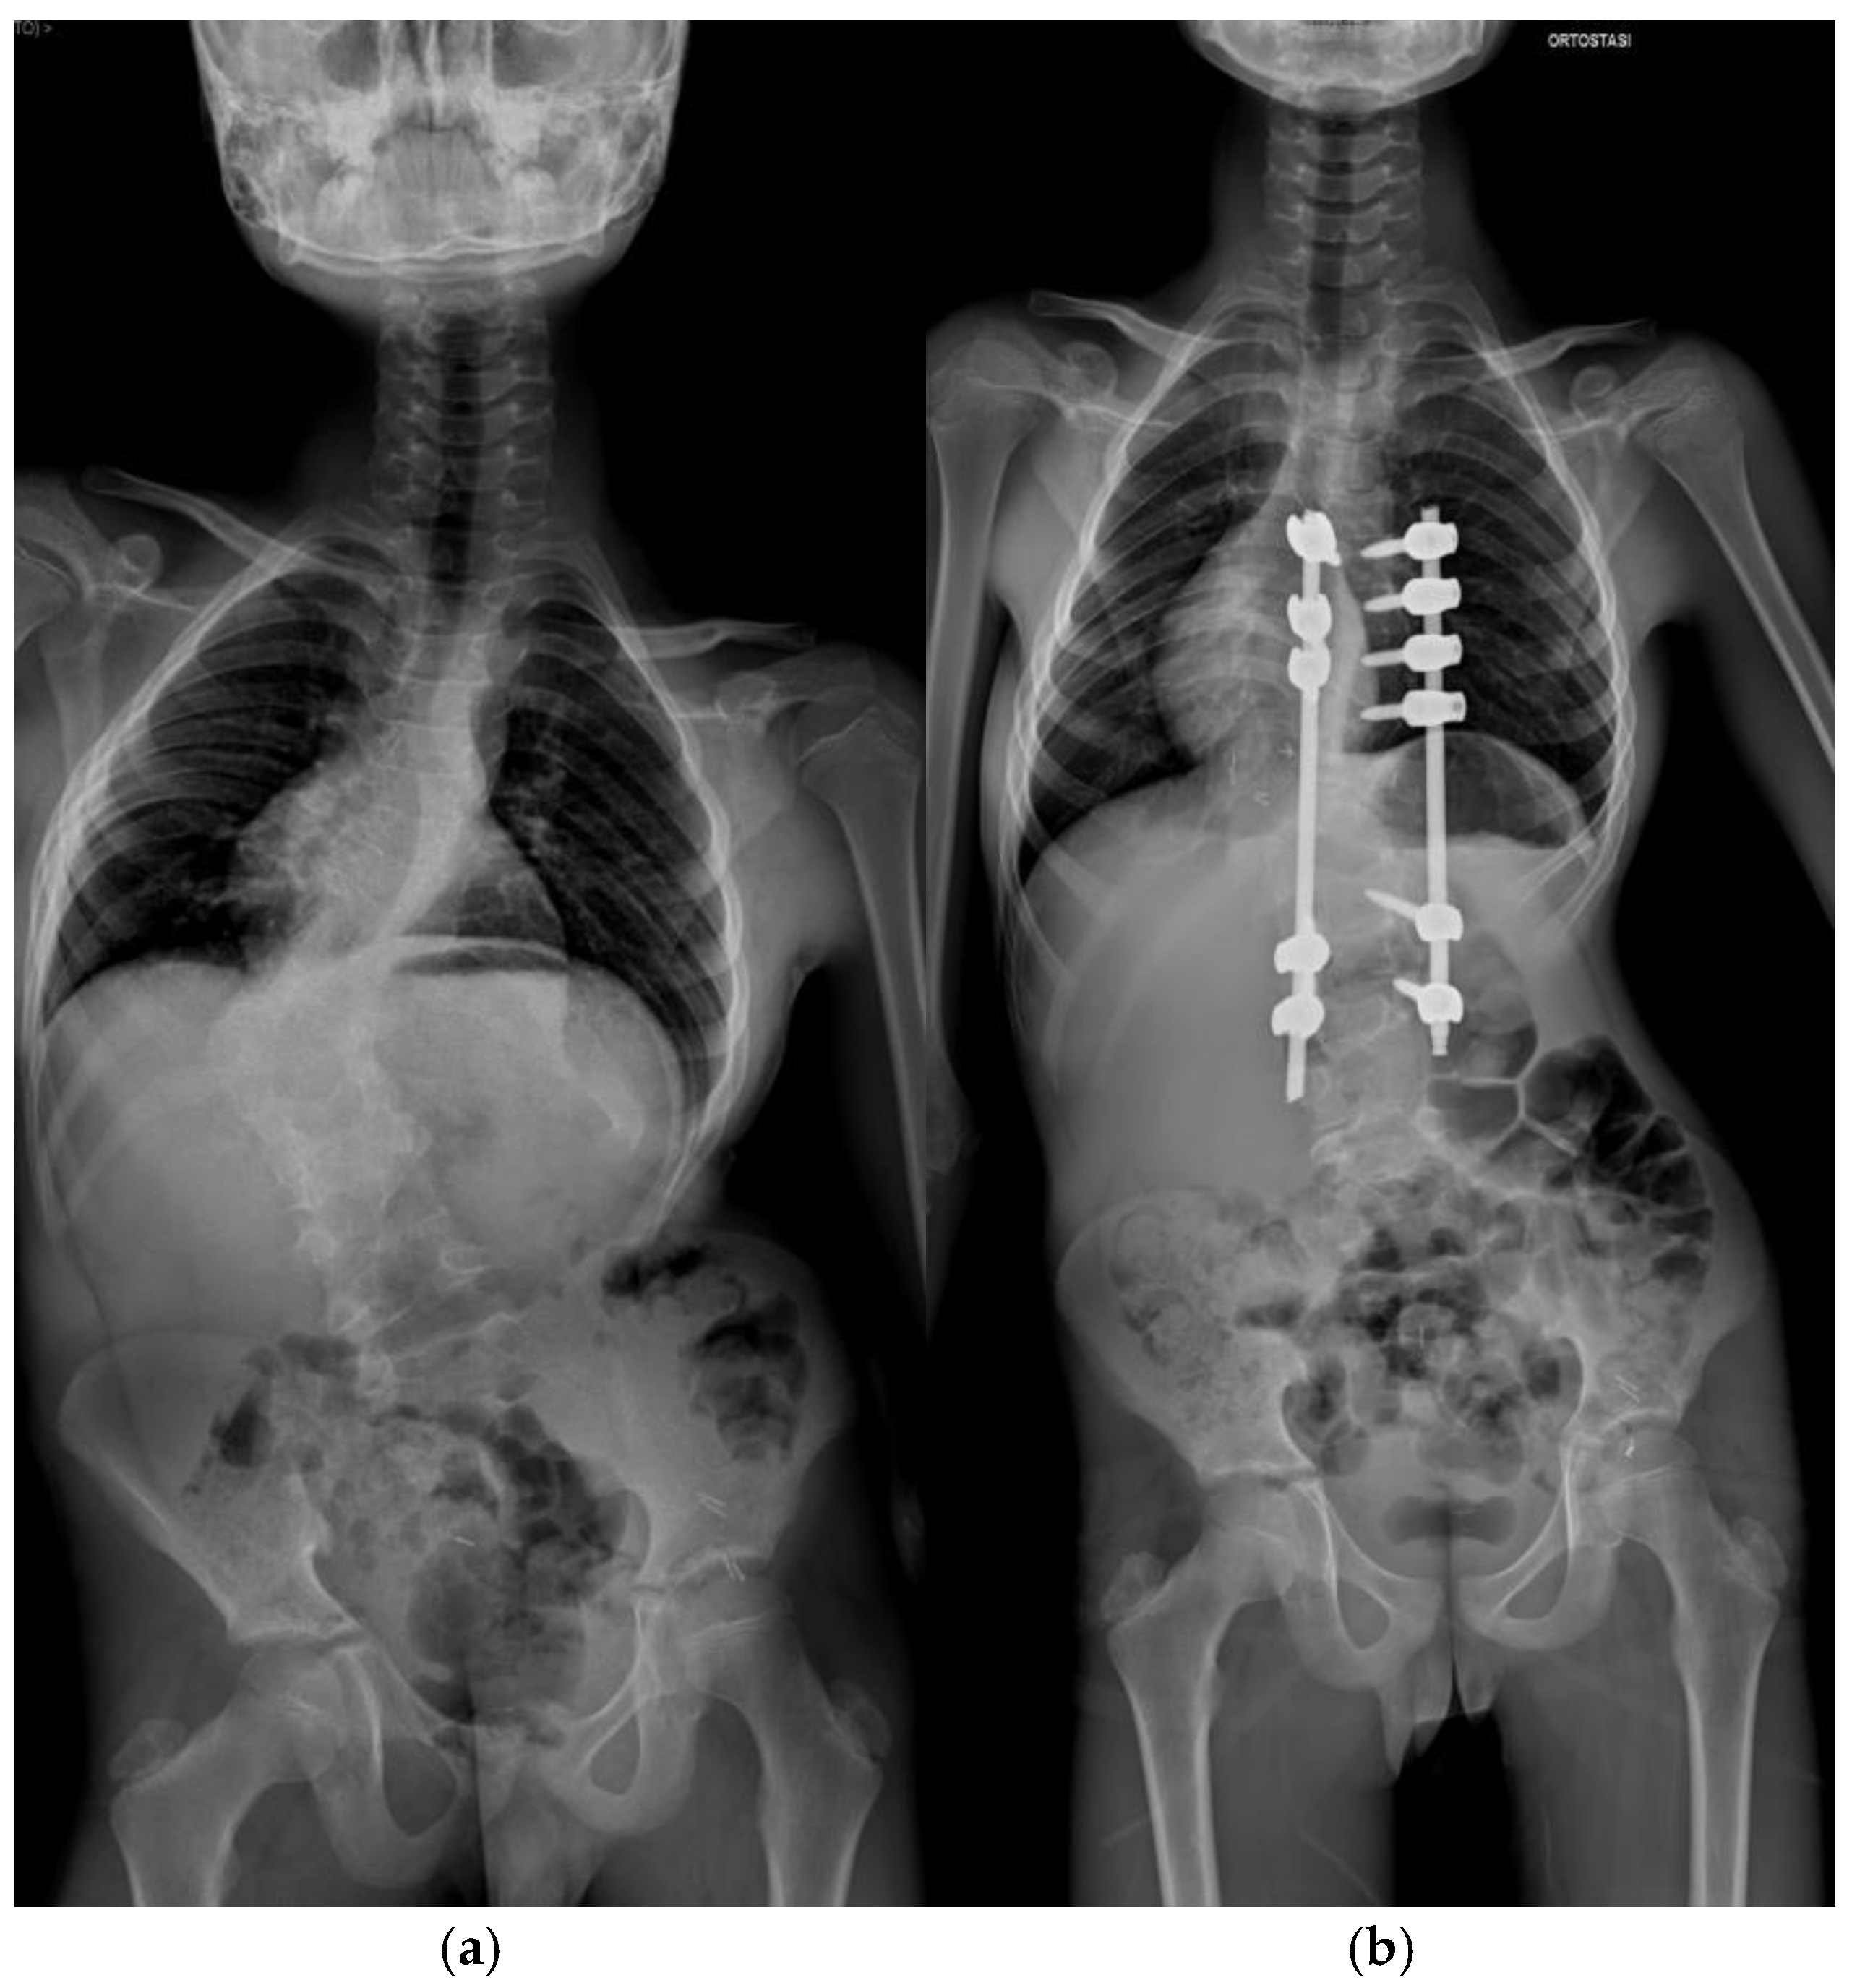

Pre-operative and post-operative radiographs documenting case 3 are reported in Figure 4.

Figure 4. Lateral radiograph of Patient 3. (a) Preoperative assessment. (b) Postoperative assessment.

A 14-year-old female, weighing 41 kg and measuring 141 cm in height (BMI: 20.6), was diagnosed with Pott’s disease (spinal tuberculosis) following a microbiologically confirmed vertebral biopsy in Ukraine in January 2017. She was placed on second-line anti-tuberculosis therapy, including pyrazinamide, ethambutol, cycloserine, prothionamide, levofloxacin, and capreomycin, which she continued for two years. Four years after the initial diagnosis, the patient presented to our clinic. Radiographic examinations revealed post-infectious intersomatic fusion from D12 to L5. Infectious disease consultation confirmed no active signs of infection, clearing the patient for surgical intervention.

Postoperative Course

During hospitalization, the patient experienced delayed wound healing with findings of E. coli, which was successfully treated with antibiotic therapy. Her preoperative hemoglobin level was 9.3 g/dL, and after two intraoperative blood transfusions, her hemoglobin at discharge was 11.7 g/dL. At the most recent follow-up, 3 years and 3 months post-surgery, the patient demonstrated good coronal and sagittal balance, with radiographic evidence of roof fusion. She reported no pain or neurological symptoms.